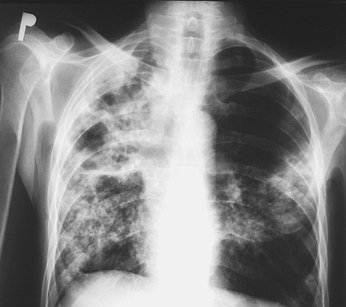

Samodzielny Publiczny Zespół Gruźlicy i Chorób Płuc w Olsztynie zaprasza wszystkich mieszkańców miasta na bezpłatne badania rtg klatki piersiowej oraz po zasięgnięcie porady lekarskiej. Akcja została zorganizowana z okazji Dni Walki z Gruźlicą i Chorobami Płuc.

Osoby, które odwiedzą szpital płucny w Olsztynie, oprócz porady lekarskiej i zdjęcia RTG płuc, będą mogły za darmo skorzystać z pomiaru cukru we krwi, oraz zmierzyć ciśnienie krwi.